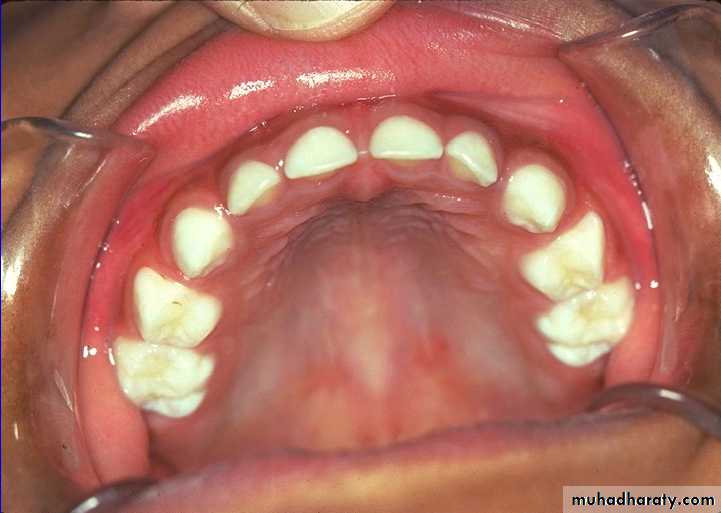

Keys to differentiating primary and permanent teeth:

Color primary teeth white and opaque

Size and contoursDepth of anatomy

Age of child

Location of teeth (counting)